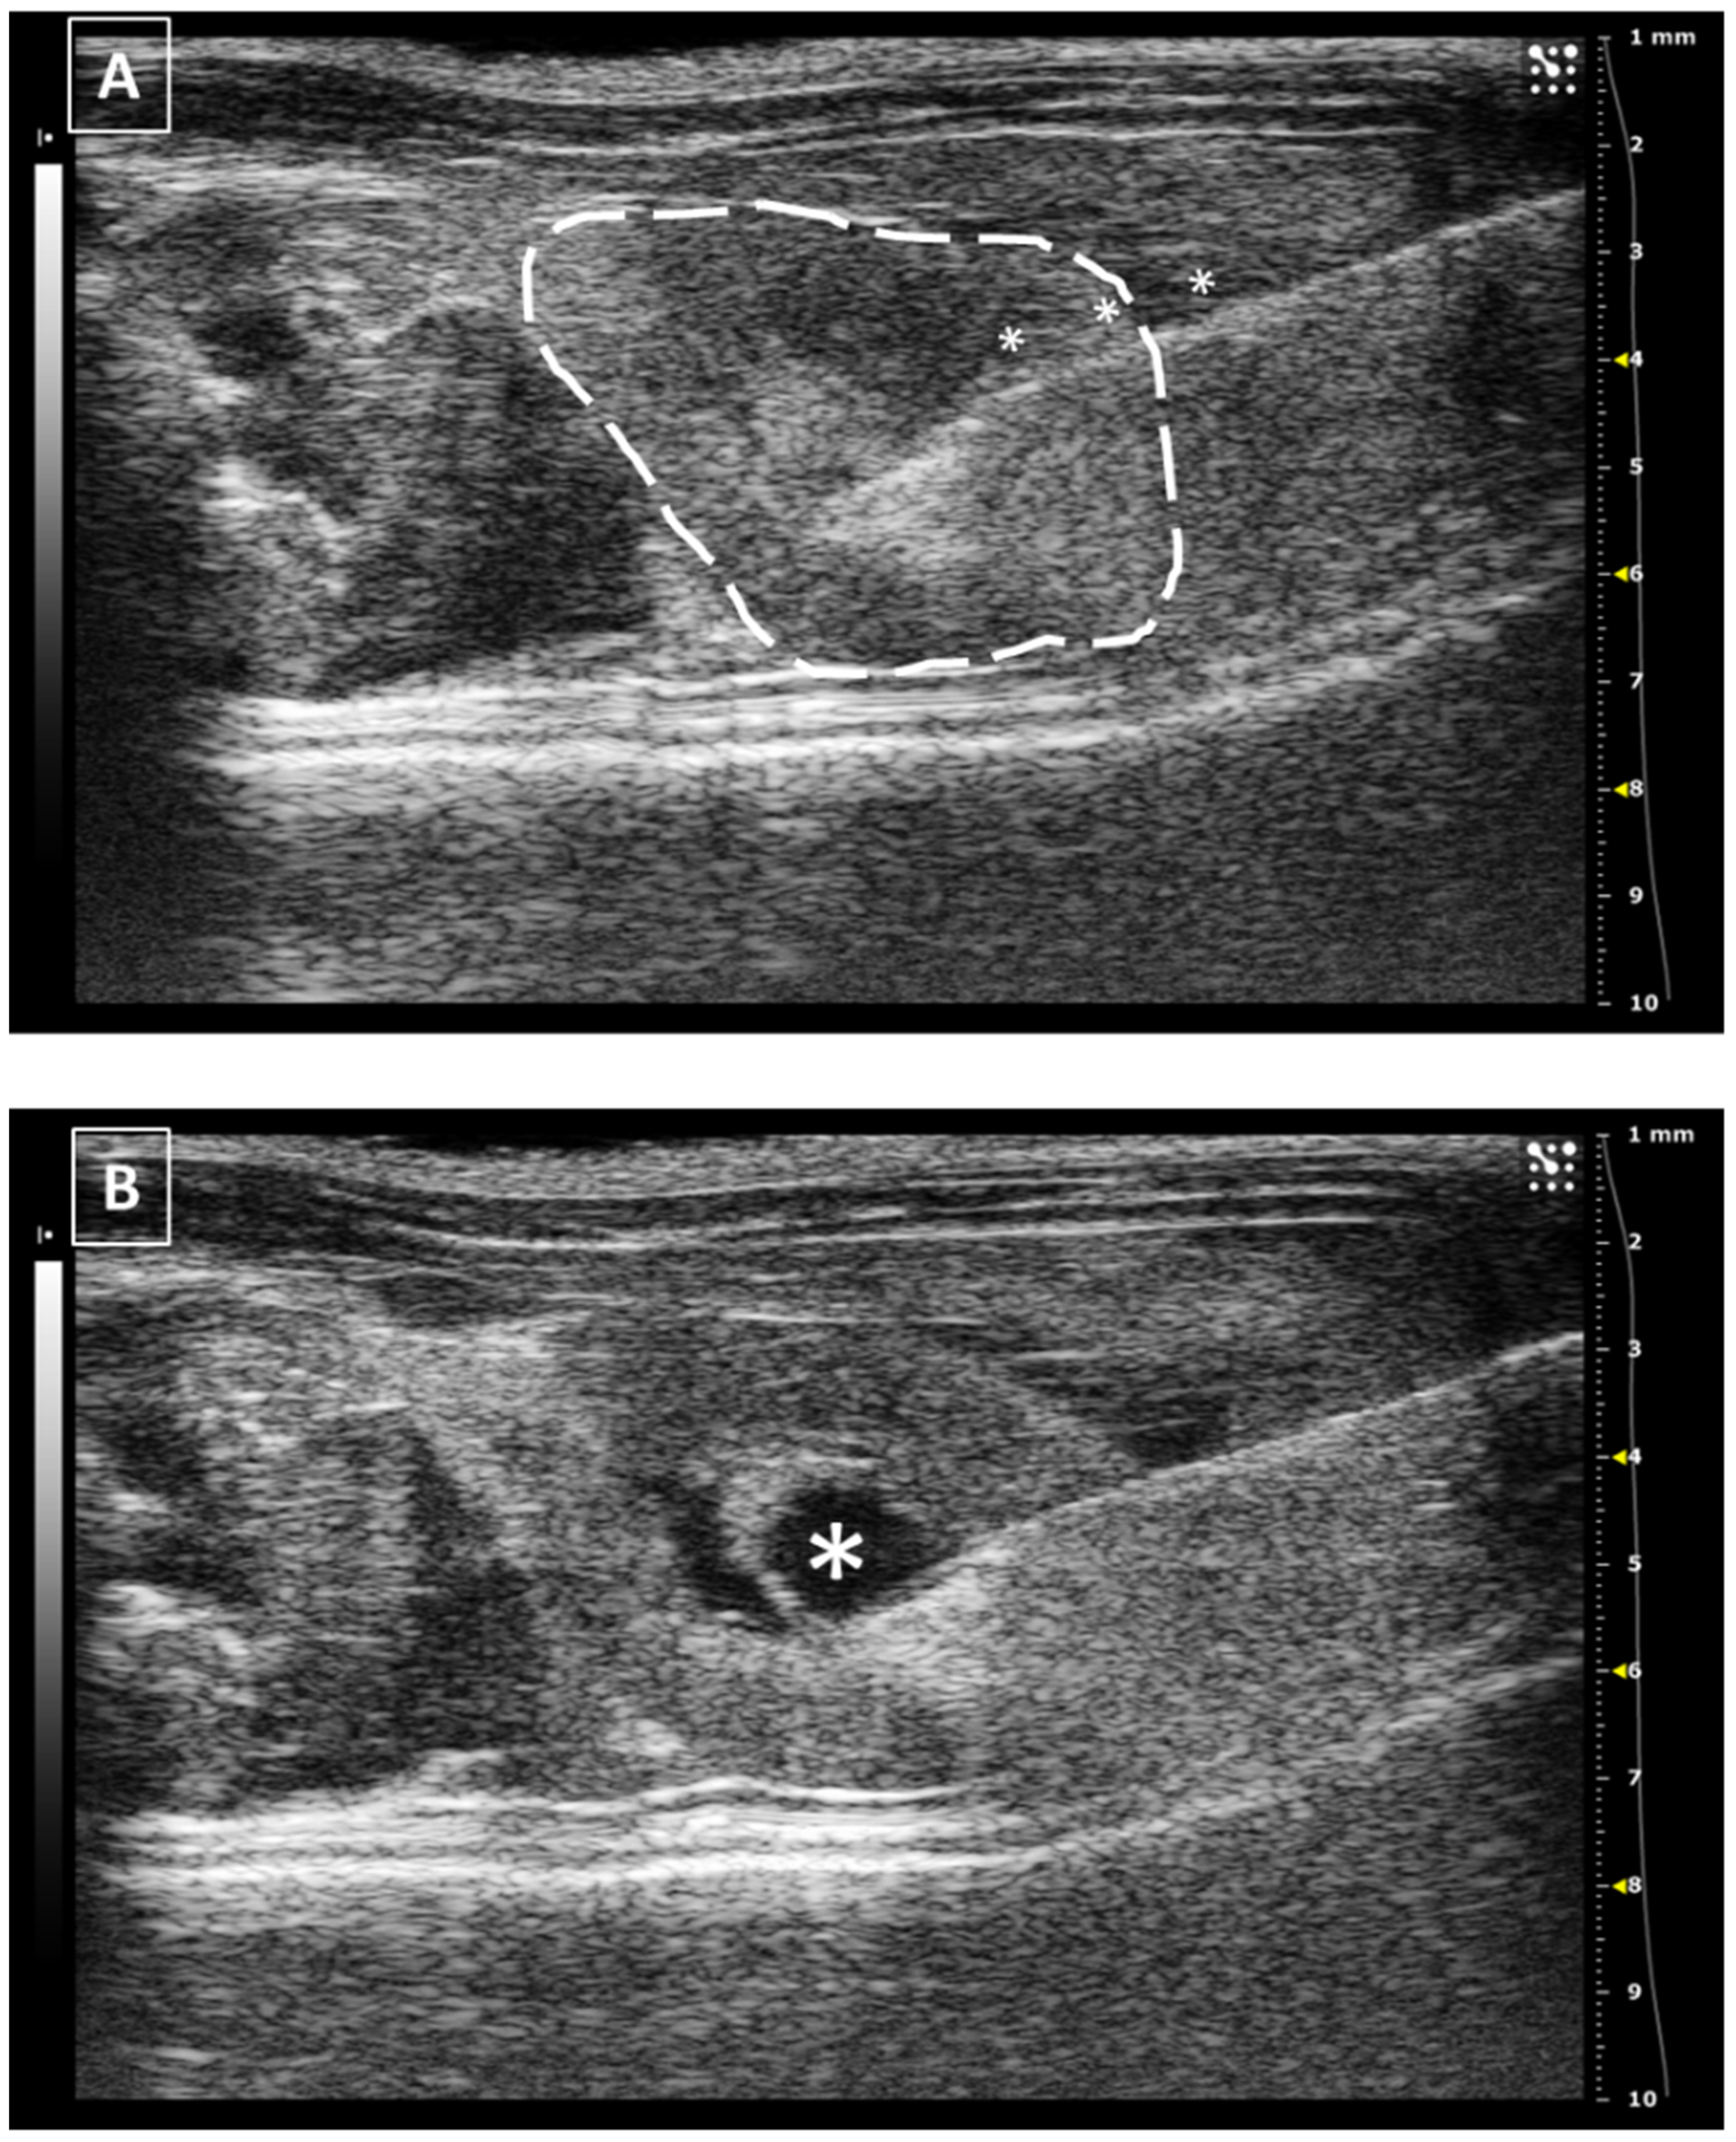

The intrarenal injection can be performed in both organs and a lateral approach is recommended, with the animal in ventral recumbency and the probe placed in the middle line of the abdomen. This layout will give us access to the lateral aspect of the kidney, safe from the ilium where the renal artery and vein are located. Depending on the injection depth, we will make a cortical (more superficial) or a medullar (inner part) injection. In both cases, the needle needs to be introduced from the lateral side and will appear in the monitor from the right side (if we inject the left kidney) or the left side (if we inject the right one) as far as we follow the scanning standardization.

The injected fluid will be observed as a hypoechoic accumulation inside the echoic renal tissue. The maximum volume that we can inject is limited to 20–50 microliters if we attend to the published works [35,36]. The renal tissue is rigid and fragile and does not accept significant increments in the tissular pressure.

In the same way as the liver and spleen, the kidney biopsy can be performed following the same approach as the injection but pulling the needle plunger instead of pushing it down. Multiple samples can be collected in both the cortical and medullar areas of the organ. An example of a renal injection is shown in Figure 7.

Once the testicle is fixed into the scrotum, the lateral approach is the best for the injection. Placing the scanning probe in a ventral position over the scrotum, the structure can be defined echographically as hyperechoic, homogenous and circular in shape. The lateral approach is the best for injecting into the testicles, placing the probe in the middle line of the body over the scrotum. For reducing the potential movement of the organ, we can use forceps for fixing the skin while piercing with the needle. Introducing the needle in the testicular stroma is easy due to its softness and it can be seen as a hyperechoic line with several comet tails artifacts in a hyperechoic background. The injected fluid will arise as an anechoic accumulation in the testicular stroma. After the injection, we should keep the needle in place for some seconds before removing it. An example of a testicular injection is represented in Figure 9.

The maximum injected volume ranges from 20 to 50 microliters if we attend to the previous publications [44,45]. The testicle is a soft and flexible tissue with a significant capability to increase its volume so the possibility of a tissular rupture can be considered low but not inexistent.

Figure 7. Intrarenal injection. (A) Injection of the needle into the kidney. Needle is marked with white asterisks and the kidney is surrounded by a dashed line. The injection is performed in the medullar zone of the organ. (B) Administration of the fluid, that is marked with a white asterisk. Images obtained at 40 MHz frequency.

Figure 9. Intratesticular injection. (A) Injection moment. The needle is marked with white asterisks and the testicle is surrounded by a dashed line. The penis bone is marked with a white arrow. (B) Administration moment. The fluid collection is marked with a white asterisk. Images obtained at 40 MHz frequency.